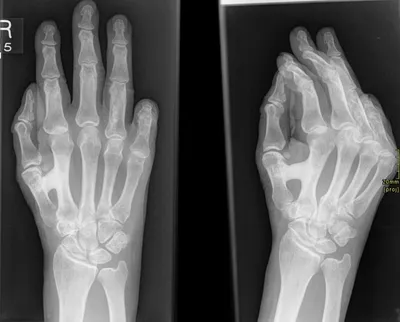

Dysplasia Radiology Images

Browse 5 medical images tagged with dysplasia. This collection includes various imaging modalities for medical education and reference.

- This collection contains 5 radiology images related to dysplasia, including various imaging modalities such as X-rays, MRIs, CT scans, and ultrasound images commonly used in medical diagnosis and education.